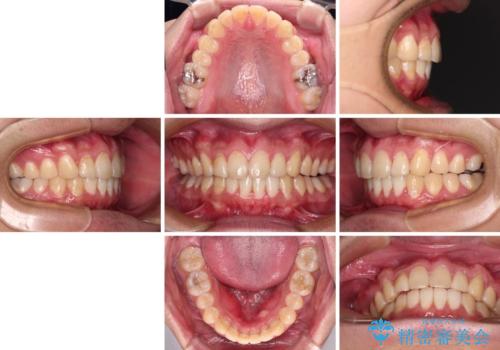

- 上下前歯のデコボコを気にして来院された患者様です。

前歯のデコボコ以外に左側の奥歯の咬み合わせに問題がありましたが、価格を抑え、短期間で気になる前歯を治したいとのことでした。

写真より左側臼歯の咬合がタイトではないことが分かりますが、こちらは保定期間に徐々に咬合させていくこととしました。